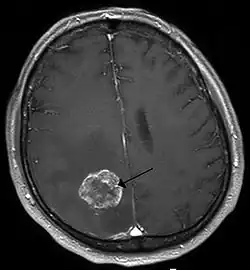

| Brain metastasis in the right cerebral hemisphere from lung cancer, shown on magnetic resonance imaging | |

Imaging

Medical imaging plays a central role in the diagnosis of brain tumors. Early imaging methods – invasive and sometimes dangerous – such as pneumoencephalography and cerebral angiography have been replaced by non-invasive, high-resolution techniques, especially magnetic resonance imaging (MRI) and computed tomography (CT) scans.[42] MRI with contrast enhancement is the preferred imaging test in the diagnosis of brain tumors.[24][43] Glioblastomas usually enhance with contrast on T1 MRI weighted MRI imaging, and on T2 with FLAIR imaging showing hyperintense cerebral edema.[24] Low grade gliomas are usually hypointense on T1 MRI, and hyperintense with T2 with FLAIR MRI. Meningiomas are usually homogenously enhanced with dural thickening on MRI.[24]